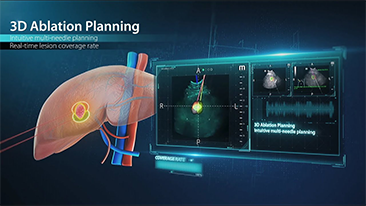

Jak wyra?nie mo?na zobaczy? w?trob??

W przypadku ogniskowych zmian w w?trobie, takich jak naczyniaki czy nowotw├│r w?troby, obrazowanie USG z kontrastem odgrywa wa?n? rol?. Technologia obrazowania USG z kontrastem UWN+ mo?e pom├│c uzyska? lepsz? penetracj?, lepsz? jako?? obrazu z ni?szym indeksem mechanicznym MI oraz d?u?szy obserwowany czas perfuzji.